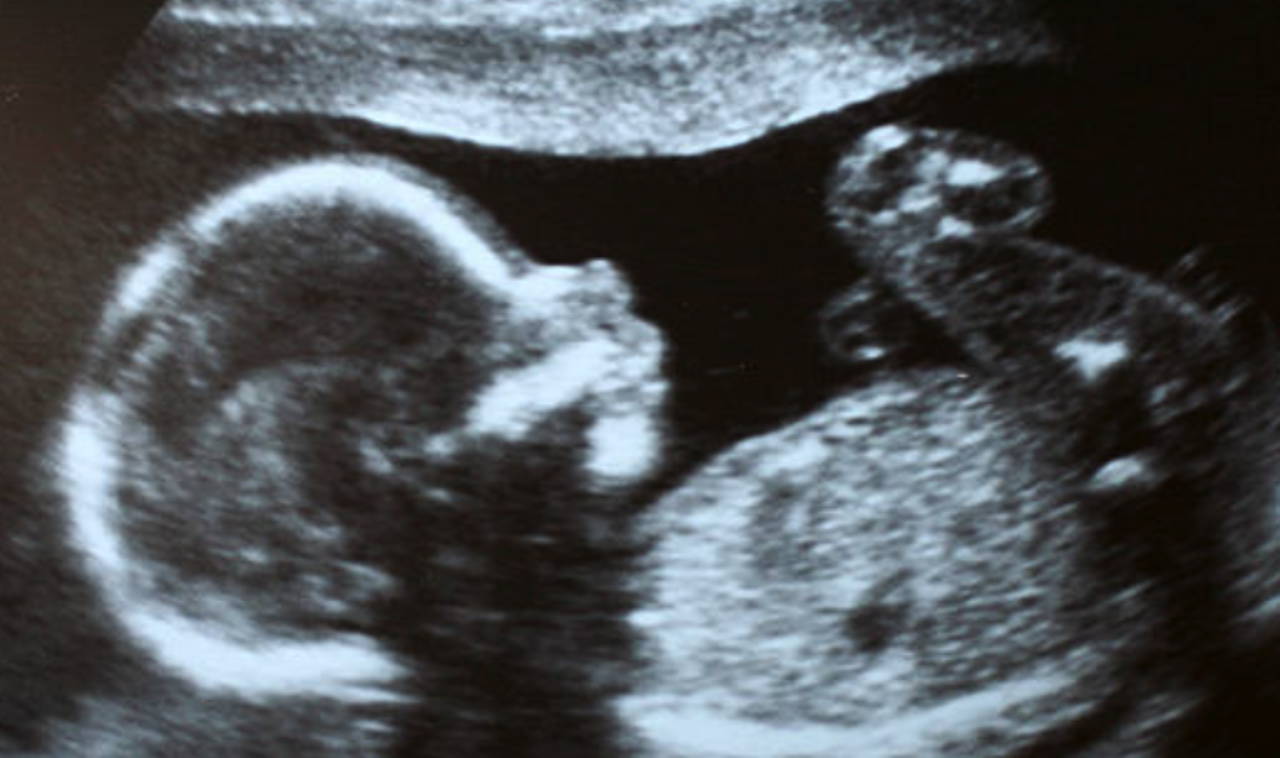

Yeni bir çalışma, Çin'de 1 yaşındaki bir kızın beyninde keşfedilen doğmamış bir ikizinin olağandışı vakasını detaylandırdı. Bu vaka olağanüstü derecede nadir olsa da, tıp literatüründe ilk kez bildirilmiyor.

Chip'te aktarılan vaka raporunda çok fazla ayrıntı bulunmasa da, cerrahi olarak çıkarıldığı ve nadir görülen bir “intraventriküler fetus-in-fetu” vakası görüldüğü belirtiliyor. Başka bir deyişle, çocuğun doğmamış ikizinin cenini kafatasının içinde yer alıyordu. Küçük “fetiform kitlenin”, üst uzuvları ve hatta parmak benzeri çıkıntıları büyütmüş gibi görünüyor, ancak neredeyse hiç gelişmemiş durumdaydı.

Bunun gibi fetus-in-fetu vakalarının, ikiz gebeliğin çok erken evrelerinde, döllenmiş bir yumurta tarafından yapılan bölünen hücre kümesi olan blastokistin düzgün bir şekilde ayrılmadığı durumlarda ortaya çıktığı düşünülüyor. Bunun sonucu olarak, erken dönemde embriyolardan biri diğeri tarafından sarılıyor.

Fetus-in-fetu vakaları son derece nadirdir. En güvenilir tahminler, bunların her 500.000 doğumda bir gerçekleştiğini öneriyor, ancak bu sayıya nasıl ulaşıldığı net değil. Çoğu durumda, doğmamış fetüs canlı bebeğin vücudunda bulunur, bu nedenle beyni etkilediği durumlar son derece nadirdir.